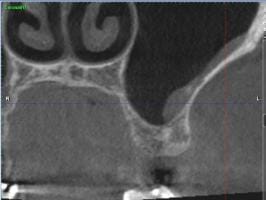

Esta semana me hicieron un tac, porque en la orto y en la radiografía periapical no salía nada. Le adjunto imágenes del mismo, y le agradecería enormemente su opinión.